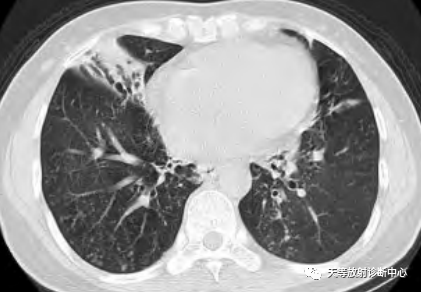

NTM-PD感染较继发性肺结核双肺分布更为广泛,多累及右肺中叶和左肺上叶上舌段和下舌段,支气管扩张、薄壁空洞伴同侧肺叶肺段卫星病灶多提示 NTM感染[2-3]。

小叶中心结节( 树芽征) 、肺小叶实变、肺段及肺大叶实变、空洞、支气管扩张、病灶内钙化灶、肺不张、肺气肿、肺大疱、肺损毁、纵隔肺门淋巴结肿大( 气管隆突下淋巴结直径≥1.5cm,其他纵隔内淋巴结直径≥1.0cm) 、淋巴结钙化、胸腔积液、胸膜增厚。

4、肺不张、肺气肿、肺大疱、肺损毁、纵隔肺门淋巴结肿大、淋巴结钙化、胸腔积液等CT征象在4个菌种组均少见。

3、空洞是4个菌种组中常见的CT征象,空洞是由支气管壁及周围炎症形成结节,管壁溃疡坏死后,坏死物经支气管排出后形成。堪萨斯分枝杆菌组出现空洞的比 例要明显高于其他3组,而且空洞更多见于右肺上叶。不同菌种组中空洞的好发部位有其特征性,空洞的发生部位对判断各菌种有一定意义。

▲NTM的厚壁空洞

胞内分枝杆菌肺病双肺常同时出现多种CT征象,且病灶多呈广泛分布;堪萨斯分枝杆菌肺病肺内出现的CT征象相对较单一,空洞常出现在右肺上叶是其特征性表现;鸟分枝杆菌肺病与脓肿分枝杆菌肺病的CT征象及病灶范围介于前两者之间。